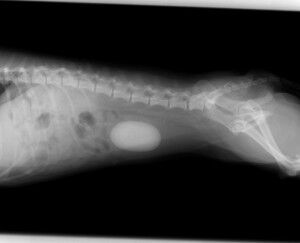

今回は膀胱結石です。

症例は7歳のシーズー(♀)です。

以前から血尿がずっと続いているということで来院されました。

尿検査を行ったところ、血液とタンパク質が出ているだけでした。

下腹部を圧迫したところ、何か硬い大きな丸いものが手に触れたので、

膀胱結石に間違いないと判断し、レントゲンを撮りました。

それが下の写真です。かなり大きな膀胱結石が存在していました。